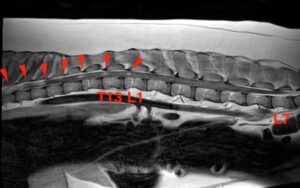

![[腰部矢状断像 造影後T1強調画像]](https://saitovet.com/wp-content/uploads/2025/09/0-300x188.jpg)

背骨の中(脊柱管)のかなり広い範囲、特に胸のあたりに白くうつる病変が見つかった。

ひどい部分では正常な脊髄が見えないほど、脊柱管内を腫瘍が埋め尽くしている。